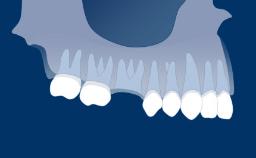

O momento em que os implantes são colocados em função é marcado pela conexão da prótese ao implante. A escolha do protocolo de carregamento mais adequado é um passo importante no processo de planejamento do tratamento. Ao selecionar o momento da reabilitação com implante, você se depara com uma importante decisão clínica. Este módulo apresenta os diferentes critérios para escolher os protocolos de carregamento.

- reconhecer os modificadores de tratamento que influenciam a seleção de protocolos de carregamento

- selecionar o protocolo de carregamento apropriado de acordo com diferentes situações clínicas